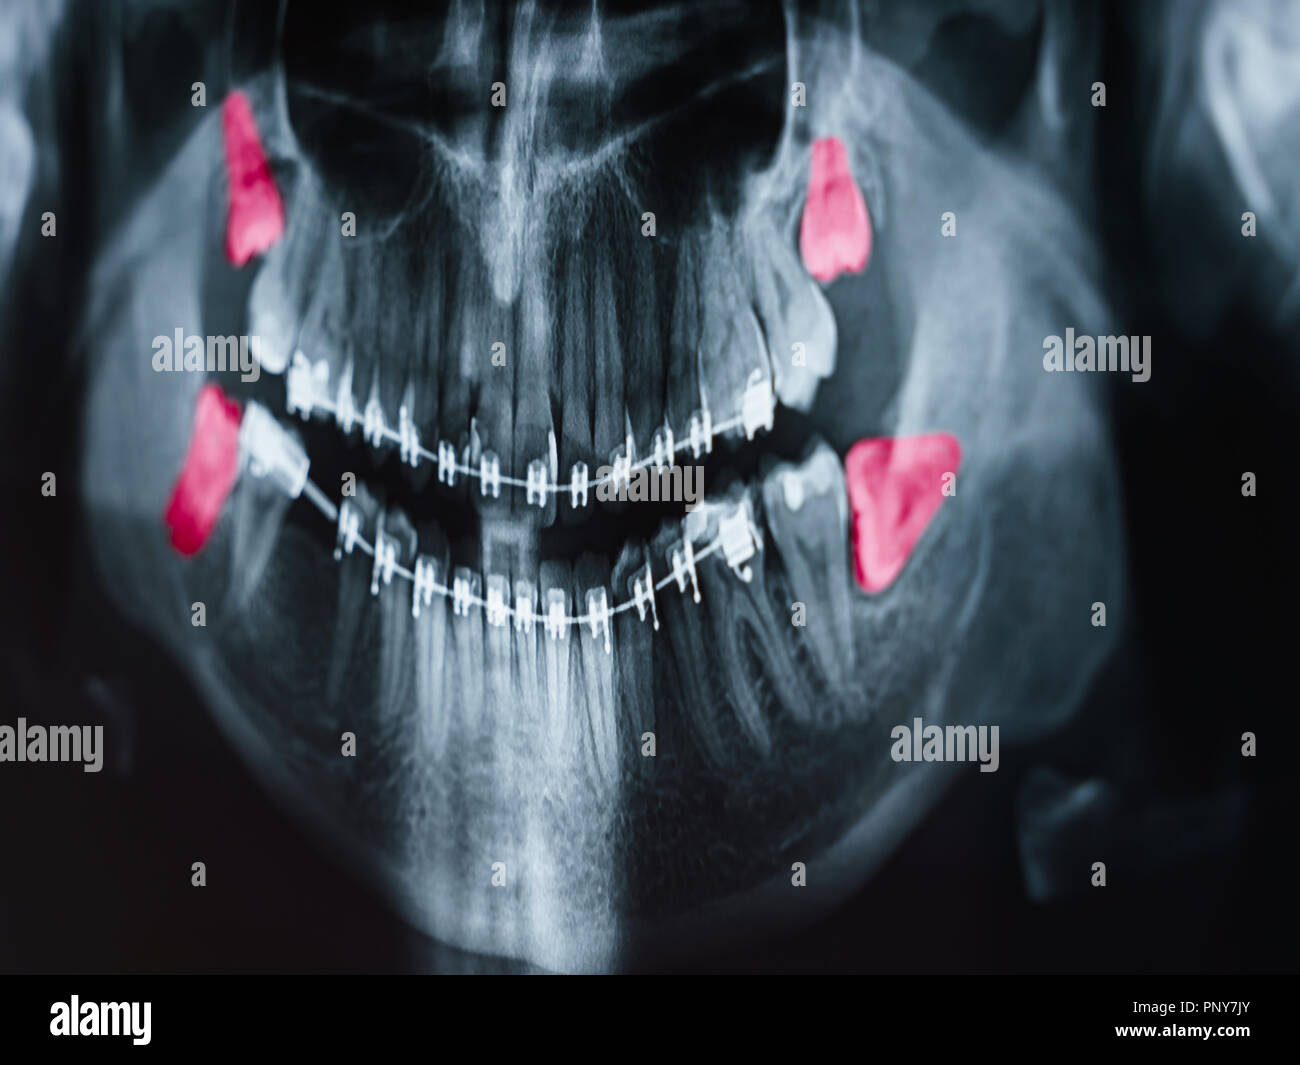

wisdom teeth on x ray Wisdom teeth ray mouth panoramic back tooth

fountainhillsdentist.comwisdom teeth ray mouth panoramic back tooth

fountainhillsdentist.comwisdom teeth ray mouth panoramic back tooth

Wisdom Teeth Eruption, Panoral X-ray - Stock Image - C013/1068

Panoramic Dental X-ray With Superior Upper Wisdom Tooth (eight Tooth

www.alamy.comtooth

www.alamy.comtooth